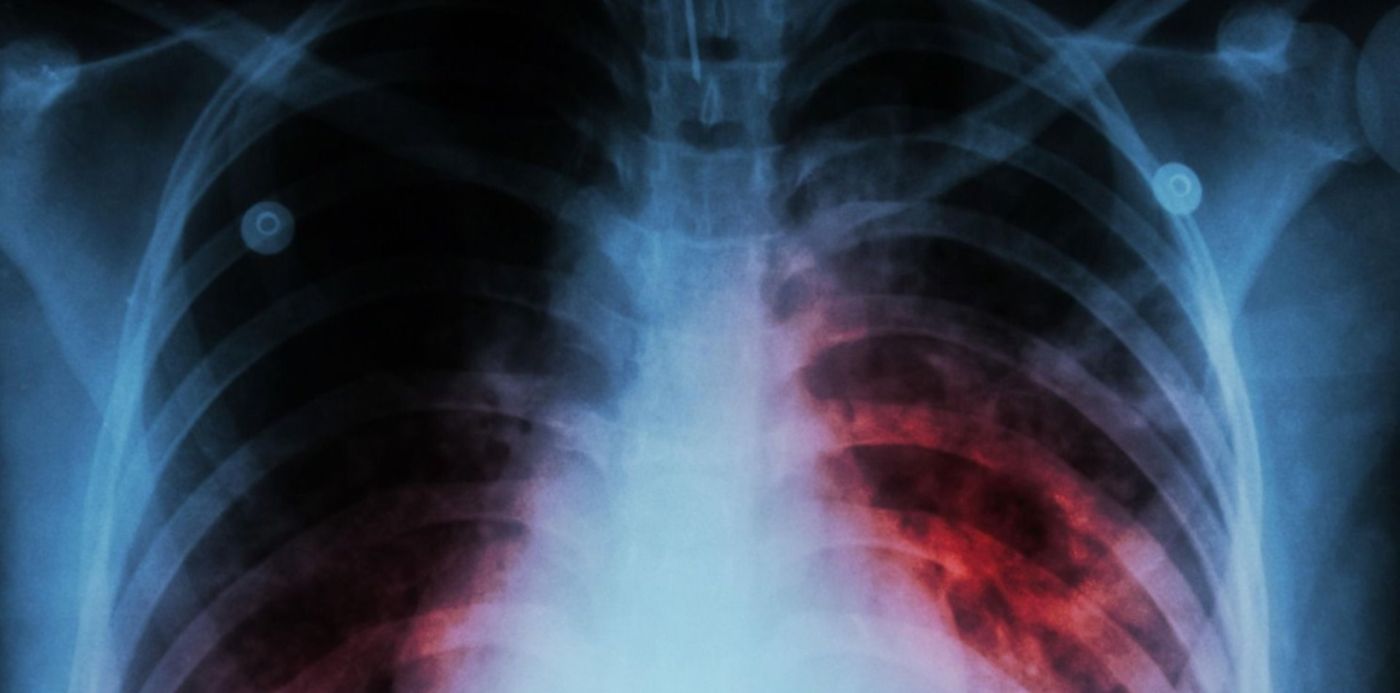

Fuentes de la Región Sanitaria XI explicaron que el presunto diagnóstico de tuberculosis sobre una alumna del secundario surge por la aparición de un "intersticio" en la placa que se le realizó a la joven. Con ese elemento, sumado a un antecedente familiar, la médica que la atendió consideró que podía tratarse de esa enfermedad y emitió la advertencia. De todos modos, aclararon que la baciloscopia, que es el estudio que se realiza sobre la mucosidad que se tomó como muestra, está aún aún en proceso, por lo que “no está confirmado que sea tuberculosis". "Los resultados van a tardar unos días, por eso no todavía no tenemos un diagnóstico", completaron.